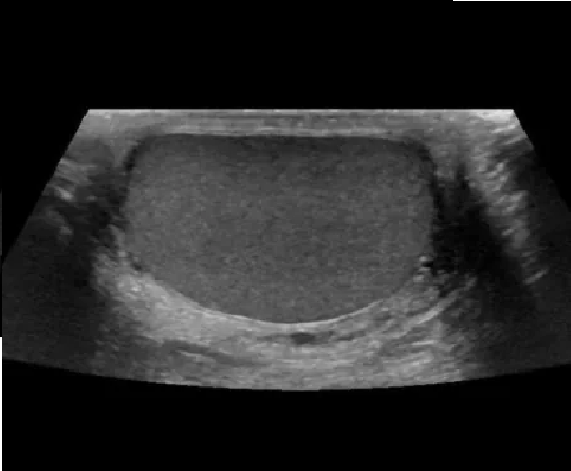

Ecografia de píloro

Indicada en bebés con vómitos persistentes. Evalúa el píloro (parte final del estómago) para diagnosticar estenosis hipertrófica, una causa frecuente de vómitos explosivos en los primeros días de vida.